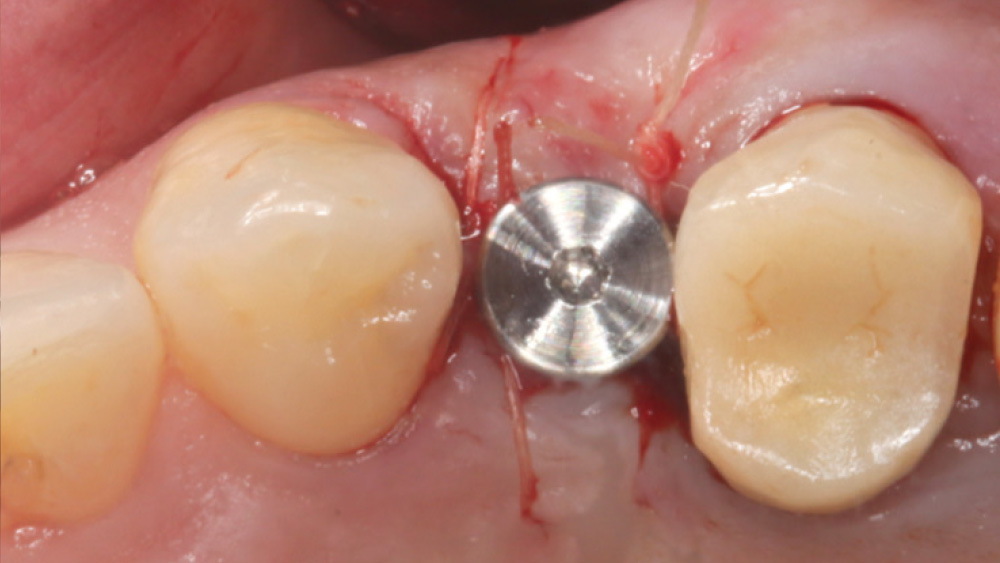

In contrast, with a flapless procedure, a tissue punch is used to gain access to the bone through the gingiva, minimizing postoperative discomfort by eliminating incisions in the mucosal tissue. Whenever mucosal tissue is incised, prostaglandin and histamine are released, resulting in potential postoperative swelling and pain. Therefore, when there is an adequate width of attached gingiva on the facial aspect of an implant site, a flapless procedure may be indicated, eliminating any suturing requirements.

The following case, which I performed alongside Dr. Stephanie Tilley of Pensacola, Florida, illustrates the use of both surgical techniques for the same patient, who presented with edentulous spaces in the areas of both right and left maxillary first bicuspids. Due to varying soft-tissue volume on each side of the arch, implant surgery was performed using a flapless procedure for one site, while the attached gingiva was reflected to expose the available hard tissue for the other. As a result of proper site evaluation, treatment planning and restorative-driven implant placement, both surgical techniques led to successful outcomes for the patient.